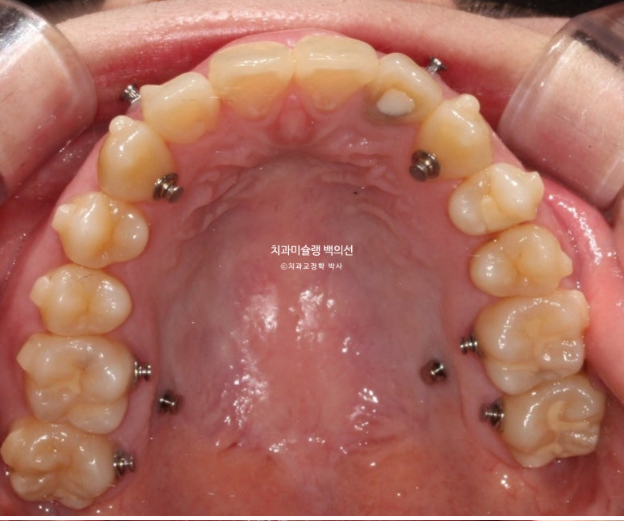

첫 세트 장치는 30개가 나왔으며 위 앞니 뿐만 아니라 어금니까지 전체치열을 후방이동하며 함입시키는 계획입니다.

교정용 나사와 고무줄을 이용하여 주도면밀한 치료계획하게 치료를 진행했습니다.

위 앞니 기준 약 2mm 합입이 되었습니다.

위 어금니도 마찬가지로 약 2mm 합입이 되었습니다.

한마디로 상악 전체치열이 2mm 합입되었고 뒤로는 약 2mm 후방이동 하였습니다.

앞니뿐 아니라 어금니까지 상악 14개 전체치열의 후방이동 및 합입으로 아래턱이 자가회전하며 턱끝이 짧아졌습니다.